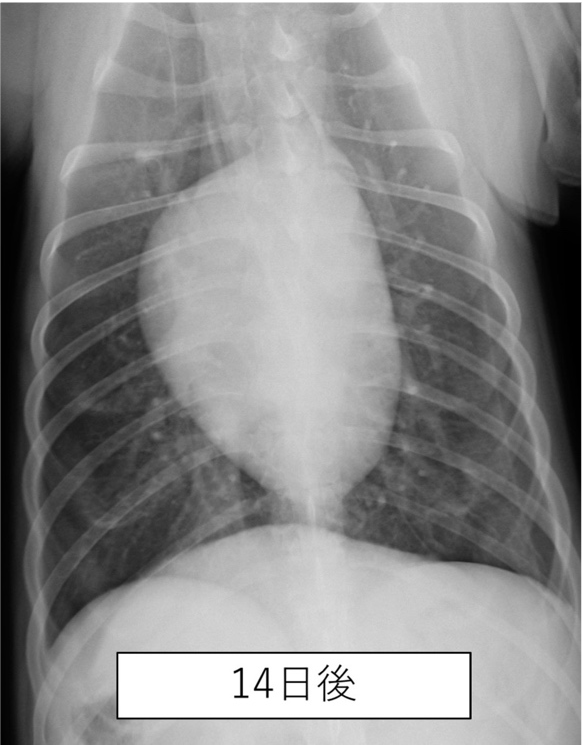

胸部のレントゲン撮影にて肺野全体の不透過性亢進(白く見える部分)が認められた。

| 誤嚥性肺炎とは、唾液や食べ物、胃液、吐物などの異物を吸引してしまうことで生じる肺炎です。加齢などにより気道反射が低下している動物や短頭種(パグやブルドッグなど)で起こりやすいと言われています。 本症例は上記の条件に当てはまりませんが、スポンジをかじる中で細かい粒子を吸い込んでしまった可能性があります。 幸いにも、本症例は抗生物質の投与により2週間ほどでレントゲン画像所見は消失し治療終了となりましたが、場合により致命的な状態まで悪化してしまうこともあります。早期発見・治療が重要です。 |